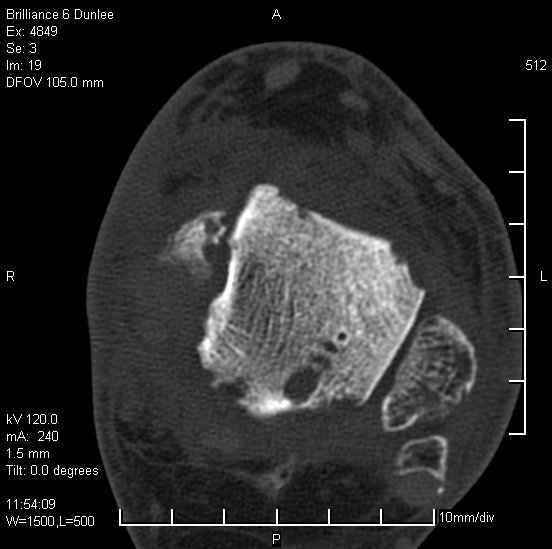

На лечении находится пациент 35 лет. Травма в сентябре 2008 г.- открытый вывих таранной кости

В день травмы ПХО, вправление вывиха, трансартикулярная фиксация. Рана зажила первично. С января нагрузка на конечность. С конца апреля- болевой синдром. На рентгенограммах и КТ признаки ас. некроза таранной кости, артроз подтаранного и голеностопного суставов.

У больного тотальный ас. некрох блока таранной кости, заинтересованы голеностопный и подтараный суставы. Эндопротезирование маловероятно на некротизированную кость. Изолированный подтаранный артродез таран не спасет.При артродезе всю некротизированную кость придется убрать.А далее замещение либо за счет большеберцовой кости, или удлинение на регенерате.